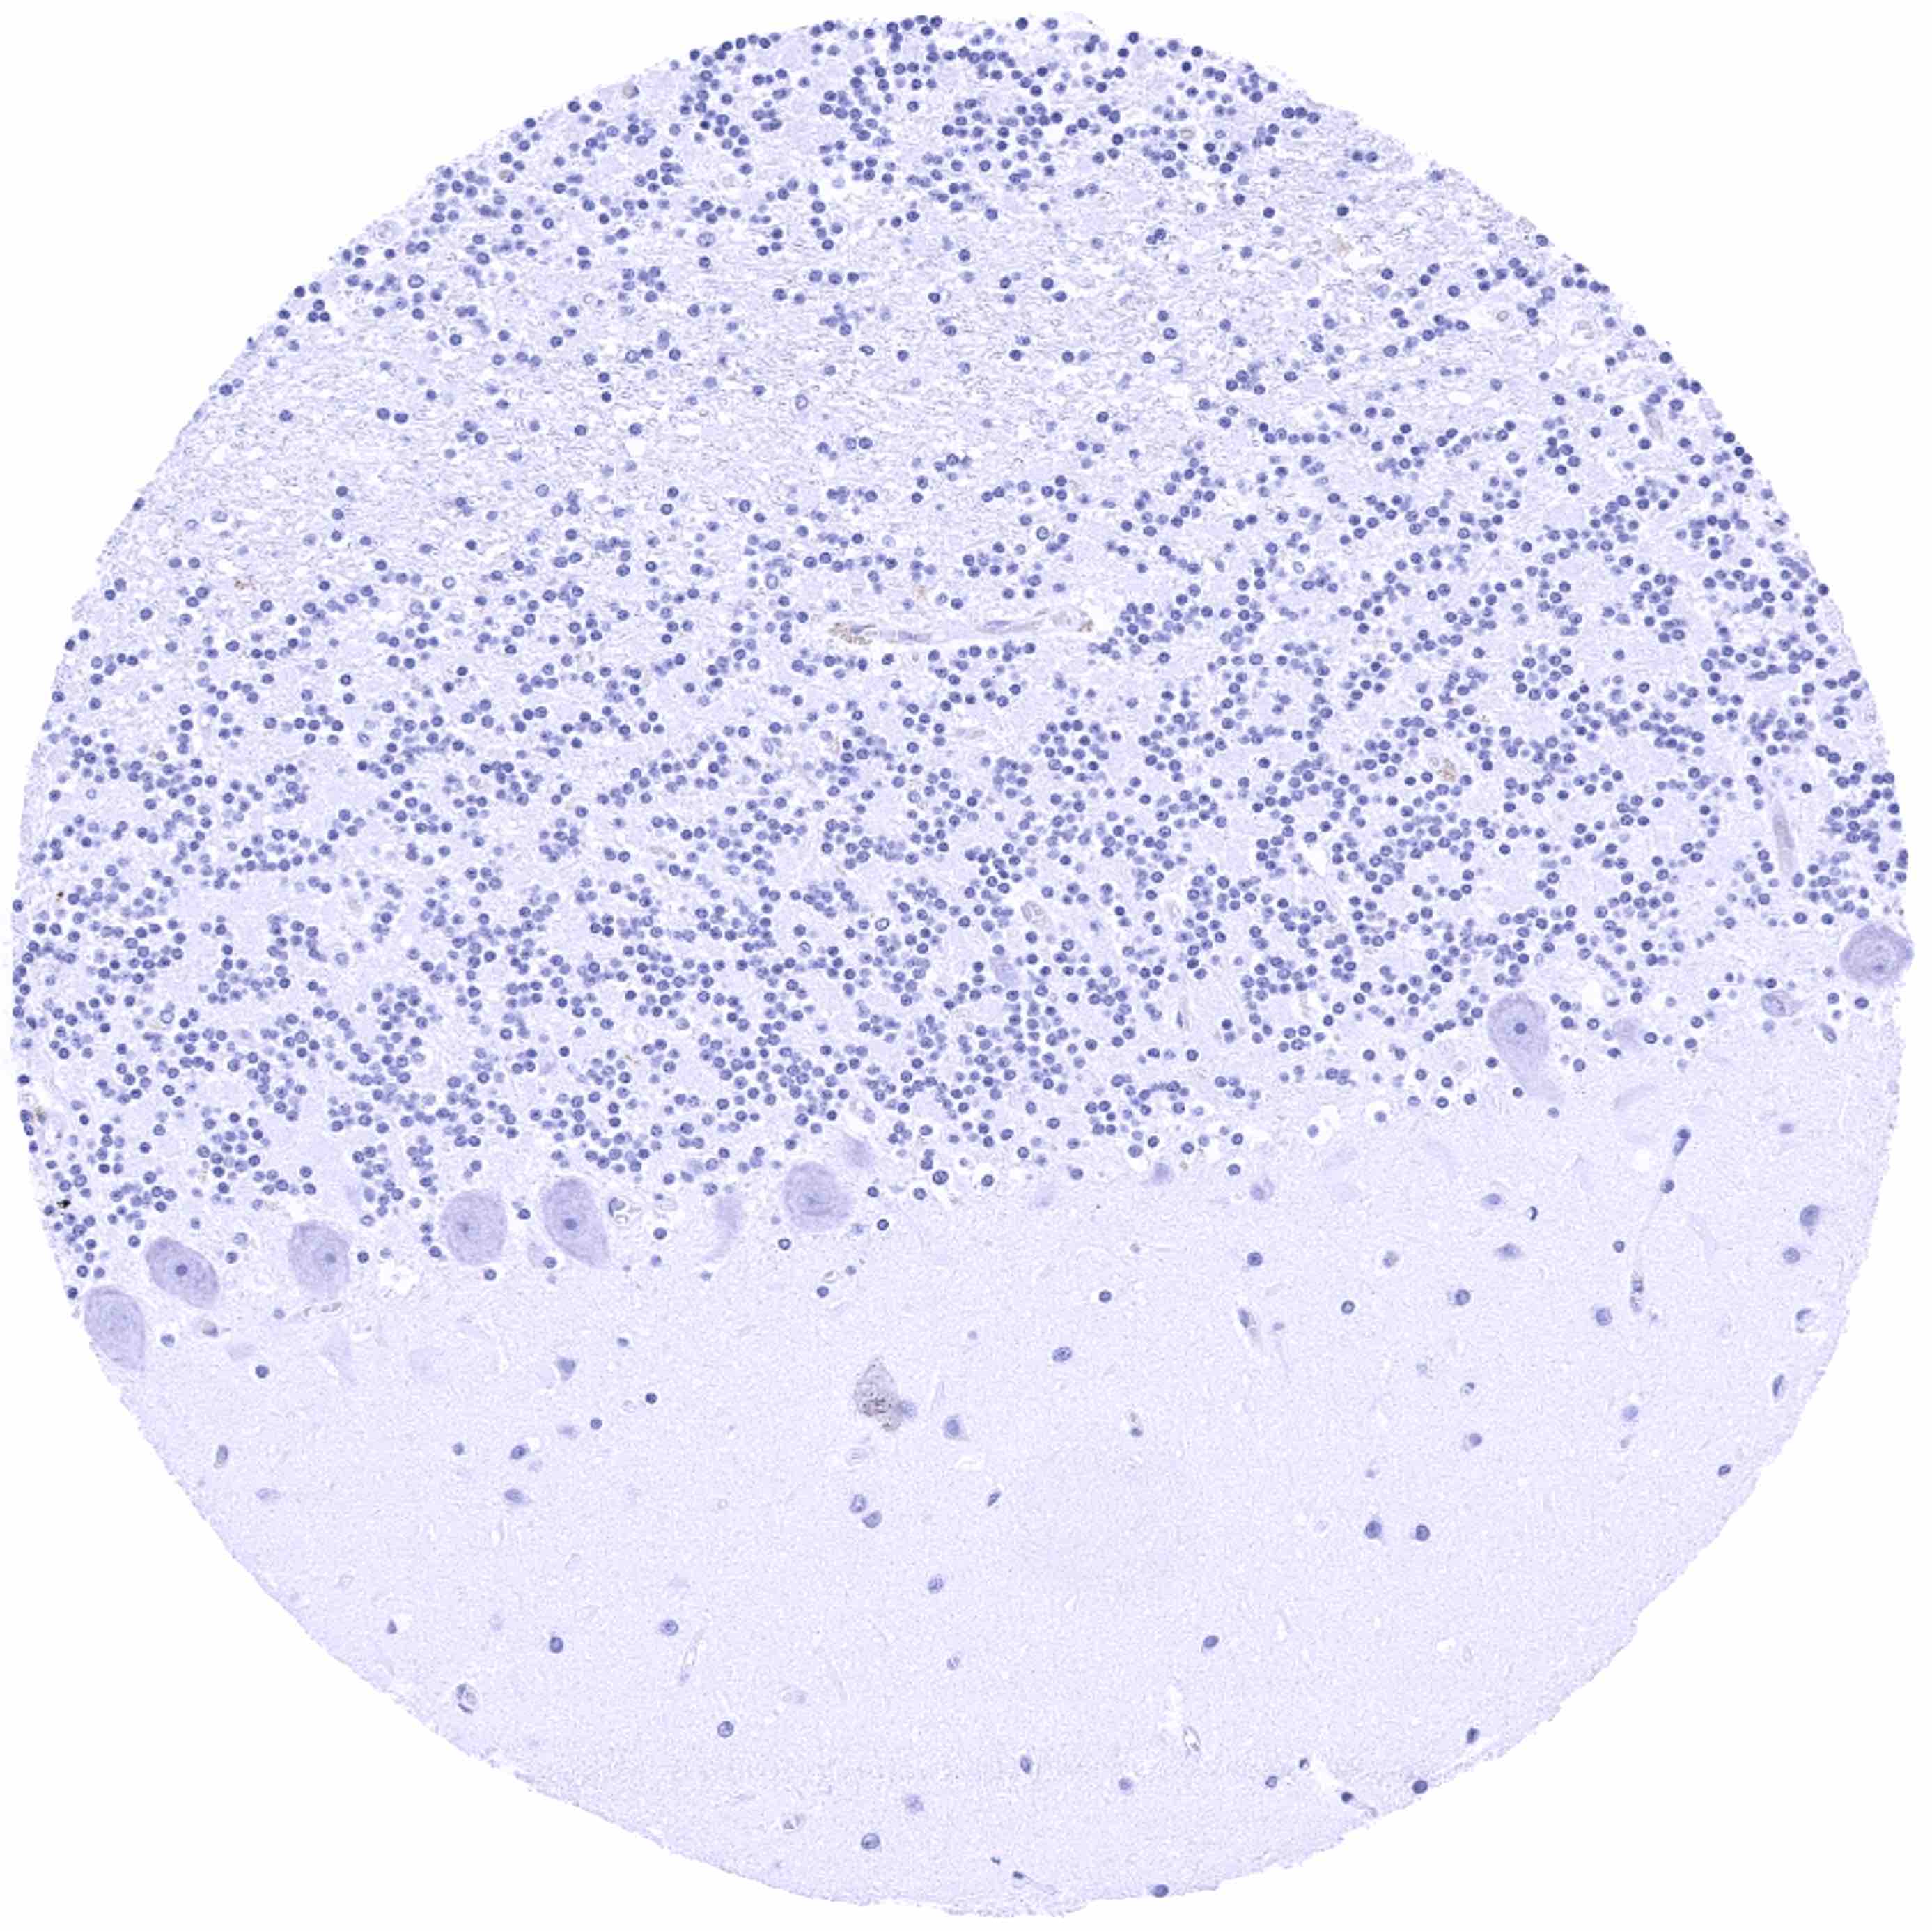

Cerebellum, cortex (molecular layer, purkinje cell layer, granule cell layer)